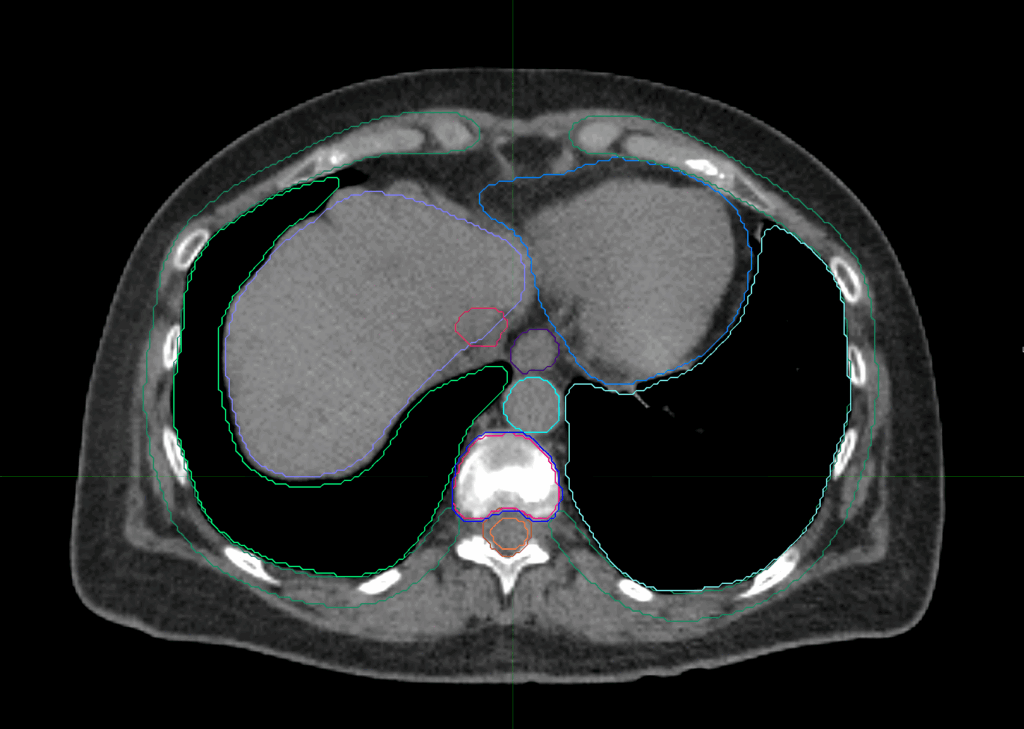

Planning CT Images

Treatment Planning Highlights

PTV(s) Volume

PTV, 45.5 cc

Dose Distributions

- Prescription to the

75.6% isodose line - Max. dose 35.71 Gy

New Conformality Index (nCI)

nCi = 1.33